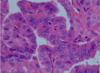

- finely dispersed chromatin impart optically clear, empty appearance “orphan annie eye nuclei” and invaginations that give the appear of inclusions, called pseudo inclusions

papillary carcinoma

- Nuclei are the key to diagnosis:

- Finely dispersed chromatin, giving them an optically clear or empty appearance

- Ground‐glass or Orphan Annie eye nuclei

- Nuclear groove

- Invaginations of the cytoplasm gives the appearance of intranuclear inclusions (“pseudo‐inclusions”)

pic

orphan annie nuclei- papillary carcinoma